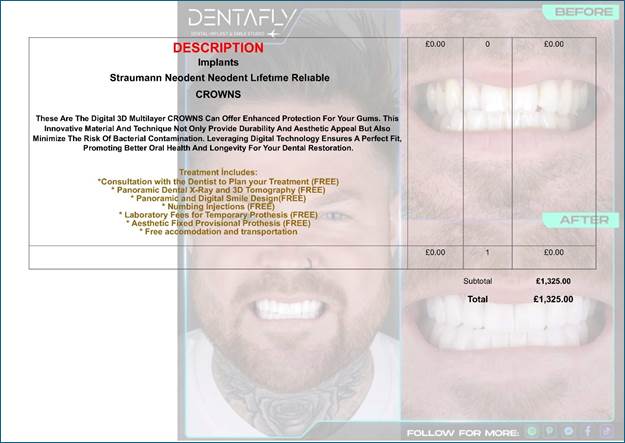

Treatment

Includes:

1.

*Consultation with the Dentist to Plan your Treatment (FREE)

2.

Panoramic Dental X-Ray and 3D Tomography (FREE)

3.

* Panoramic and Digital Smile Design (FREE)

4.

* Numbing Injections (FREE)

5.

* Laboratory Fees for Temporary Prothesis (FREE)

6.

* Aesthetic Fixed Provisional Prothesis (FREE)

7.

* Free accommodation and transportation

What

was finally agreed in my phone consultation with Dentafly was the following as

attached in a Copy of the invoice that they sent to us: --